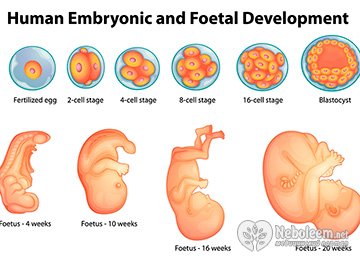

На протяжении всего срока беременности происходит сложнейший процесс внутриутробного развития плода, формирование готового к рождению ребенка из оплодотворенной яйцеклетки.

Рассмотрим, как формируется и развивается ребенок с момента зачатия, при этом важно, что первые недели роста самые значимые для жизнеспособности зародыша и его нормального развития. Внутриутробное развитие плода по неделям происходит следующим образом:

- 1 неделя – женщина зачастую еще не знает о своей беременности, но важный процесс уже начался, оплодотворенная яйцеклетка продвигается по маточным трубам. Образуется морула или зародыш, который к седьмым суткам начинает имплантироваться в полость матки;

- 2 неделя – процесс имплантации зиготы или плодного яйца продолжается, оно углубляется в опадающую оболочку и прививается, растворяя ее, начинается процесс питания зародыша. Происходит удлинение и разделение на две части первичной кишки плода, начинается процесс формирования сердца и сети крупных сосудов, изначально сердце похожу на трубку. Выглядит плод в это время как очень маленькая ягода малины;

- 3 неделя – эмбрион меняет форму и увеличивается, происходит закладка нервной системы, формирование спинного и головного мозга. К 19 дню зарождаются первые клетки крови, сердечная трубка делает первые сокращения на 20 день. Формируются глазные ямки, из которых впоследствии образуются глаза малыша;

- 4 неделя – длина плода 0,1мм, разрастается мозг, закладываются зачатки пяти его отделов, одновременно идет закладка зачатков легких, печени, кишечного тракта, почек, внутреннего уха, мышечных тканей. В этот период внутриутробного развития начинают формироваться конечности, выглядят они как маленькие почки на боках зародыша. Происходит первичное формирование рта и развитие глаз;

- 5-8 неделя – зигота переходит в стадию эмбриона, размером с песчинку (от 0,4-1,0 мм до 11мм) и весит эмбрион к концу восьмой недели уже около 13 г. Идет закладка формирования скелета и конечностей, стопы и кисти рук обретают формы. Практически сформировалось тело, есть все основные органы, а некоторые из них, например, почки и печень уже функционируют, в желудке вырабатывается сок. Начинается формирование половых органов, головка равна длине туловища и на ней хорошо заметны зачатки глаз, носа, рта;

- 8-12 неделя – с 10 недели можно говорить о внутриутробном развитии плода, поскольку начался фетальный период. Весит плод к концу 12 недели 13-14 г, а его длина около 9 см. Процесс плацентации завершен, начинают работать мышцы, которые к этому времени уже связаны с нервными клетками. Окончательно сформированы руки и ноги, у плода развивается чувство равновесия, осязание и обоняние. Сформирована перегородка, отделяющая брюшную полость от грудной клетки. Начали развиваться зачатки молочных зубов, формируется радужная оболочка глаз. Проявляются первые признаки перистальтики кишечника, а печень начала вырабатывать желчь;